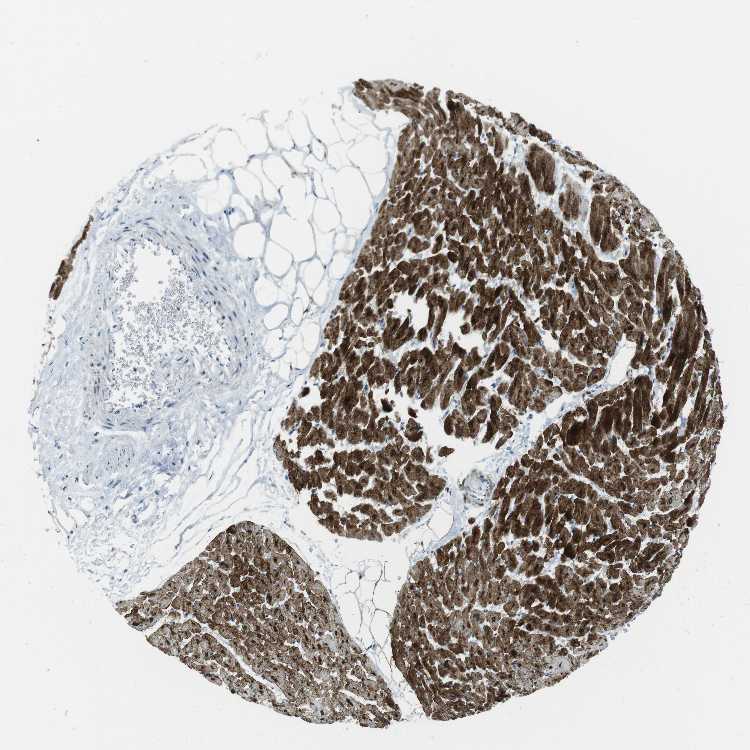

HEART MUSCLE - Antibody stainingi

Antibody staining in the annotated cell types in the current human tissue is reported as not detected, low, medium, or high, based on conventional immunohistochemistry profiling in selected tissues. This score is based on the combination of the staining intensity and fraction of stained cells.

Each image is clickable and will lead to virtual microscopy that enables deeper exploration of all samples and also displays staining intensity scores, fraction scores and subcellular localization as well as patient and tissue information for each sample.

Antibody CAB016544

Cardiomyocytes High